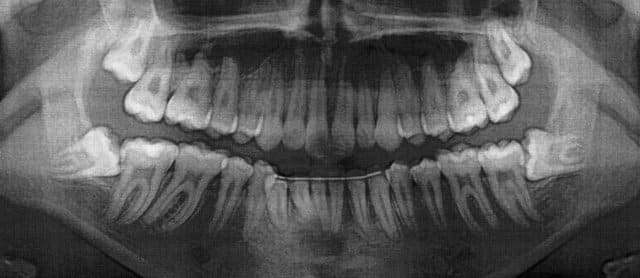

Est ce que vous extrairiez?

J'hésite: proximité du canal dentaire.

ça va, les zones de découpage de la dent sont assez loin. bon courage.

POur l'OTP1, je vois pas bien, donc pas de commentaire.

Pour L'OTP2, tu peux extraire car config parodontale défavorable à long terme, extraire maintenant car apex pas encore formés sinon risque de contact étroit avec canal plus tard. Pas de risque pourle nerf dentaire. tu découpes en autant de fois nécessaire pour tout sortir. si t'es pas sûr, tu prends ton temps et ça sortira.

Canin, es-tu sûr que c'est pas le contraire? Configuration paro défavorable sur le n°1.

Moi perso, le n°2, je le laisserais tranquille, tant que c'est sous-muqueux et asymptomatique.

Osmi,

Non je n'ai pas confondu mais ce que tu dis est vrai. La config paro est pire sur l'OTP1.Je ne vois pas bien l'image du canal mais à priori y'a pas de problème car tu est proche du canal mais au dessus. Tu ne peux odnc pas léser ton nerf sauf si tu forces lors de l'avulsion. C'est pour ça qu'il faut couper au maximum. De plus tu conserves le maximum. Le gros problème, c'est le manque d'accès en rapport avec la branche montante. Il faut que ton patient ouvre bien la bouche et alors y'a pas de problème.

Concernant l'OTP, y'a des chances que la 48 soit vestibulée et donc il doit y avoir quand même de l'os en distal de la 47. Dans ce cas si la gencive est bien kératinisée et saine, pas de poche paro, tu peux effectivement laisser. Mais bon le problème c qu'on peut jamais prévoir l'évolution de ce genre de situation. Le truc c que si la personne semble jeune genre 20 ans environ. Non ???? Si tu enlèves maintenant, la cicatrisation osseuse sera favorable. A 40 ans si il a de la paro, c moins évident et la proximitré nerveuse encore plus délicate à gérer. L'extraction faite maintenant devient donc en quelque sorte prophylactique si tu décides de l'enlever.

Concernant la 38, la config paro est pas top non plus.

Si tu penses pouvoir réaliser une chir sans problème (accès, bon état général, geste sûr) alors je crois qu'il faut enlever.